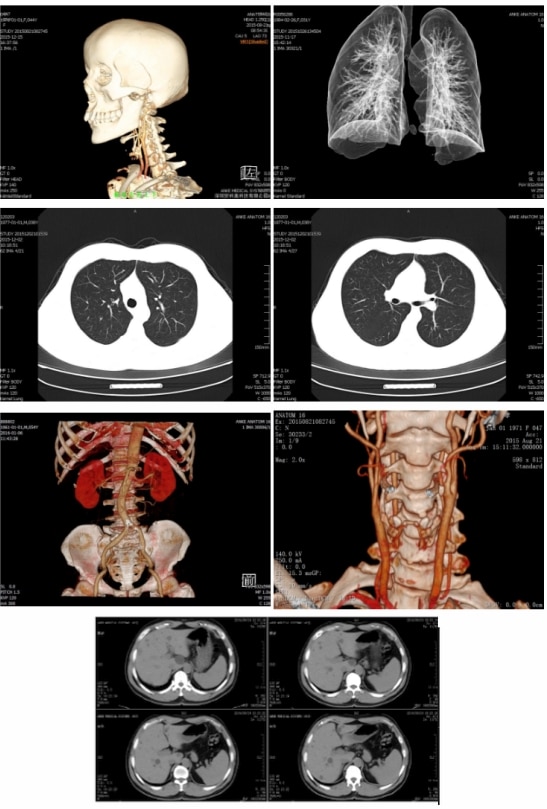

ANATOM 16 jest nowoczesnym wysokiej klasy tomografem komputerowym 16-rzędowym, który umożliwia skanowanie całego ciała.       Pionierska Technologia Gantry Wyższa prędkość cyklu Zwiększona prędkość dynamiczna Mniejszy rozmiar oraz waga Wysoka Jakość Pobierania Danych Ilość detektorów na kanał 896 * 16 Liczba detektorów urządzenia 21504 Minimalna szerokość warstwy 0.625mm Perfekcyjne Możliwośći Generatora Max. Moc Generatora 60kW Napięcie Lampy 80-140kV Natężenie Lampy 10-500mA     Innowacyjna Technologia Gantry PowerLink Bezkontaktowy Power Transfer, bez stosowania szczotek czy pierścieni ślizgowych Pełna integracja w komunikacji oraz transmisji danych Integralna kontrola obrotu gantry     Zalety systemu Adose     Natężenie Lampy jest automatycznie kontrolowane względem badanej części ciała, aby efektywnie zmniejszyć stopień promieniowania oraz zapewnić wysoką jakość obrazowania     Nowoczesna Technologia LISA     Dzięki zastosowaniu najnowszej technologii LISA pobieranie obrazów o wysokiej rozdzielczości jest już możliwe przy 70% normalnej dozy promieniowania. Dodatkowo opcja posiada precyzyjne rozwiązania dla skanowania pediatrycznego, co skutkuje redukcją promieniowania dzięki zastosowaniu dedykowanych parametrów pracy urządzenia.     Wyjątkowa jakość obrazów klinicznych Głowa: Conventional, Paranasal Sinus, MPR, SSD, VR, CTA, HD Inner Ear Cervical Kręgi szyjne: Conventional, MPR, VR, CTA Klatka piersiowa: Conventional(Lung Window, Mediastinal Window), MPR, VR, MinIP Brzuch: Conventional, Enhancement(3 Phases), MPR, VR, CTA Kończyny i Stawy: Conventional, MPR, VR     Minimalne koszty utrzymania Mniejsze dawki, mniejsze zużycie energii Bezkontaktowy Power Transfer, bezszczotkowa gantra